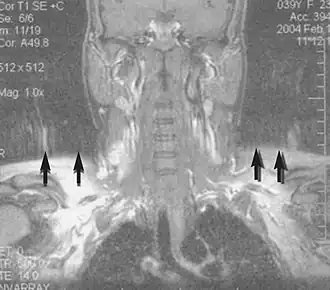

Motion artifact (T1 coronal study of cervical vertebrae)[142]

An MRI artifact is a visual artifact, that is, an anomaly during visual representation. Many different artifacts can occur during magnetic resonance imaging (MRI), some affecting the diagnostic quality, while others may be confused with pathology. Artifacts can be classified as patient-related, signal processing-dependent and hardware (machine)-related.[142]